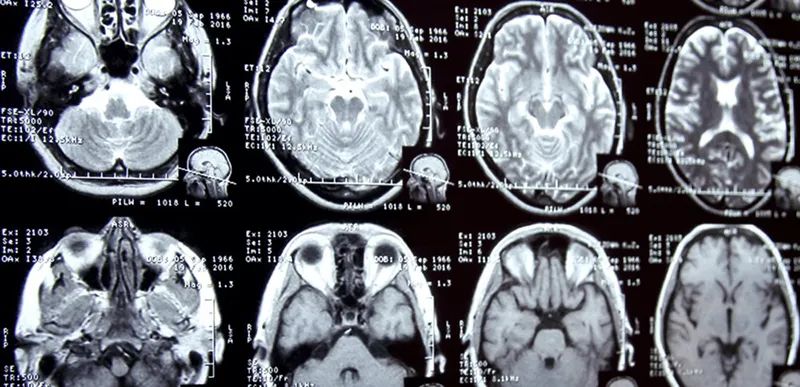

随着数据规模的增长和预训练技术的进步,生成的图像越来越逼真,模型的语义理解能力也在不断增强。为了进一步提升这些模型的性能,需要对数据进行更细致的标注,同时通过强化训练方法,如强化学习,使模型不仅能生成图像,还能理解和响应图像内容中的复杂和抽象概念。这种深层次的语义理解是未来计算机视觉技术发展的关键方向,预计将在自动驾驶、医学图像分析等应用中发挥重要作用。

生物医学领域则更加直接地将大模型应用于临床和医疗研究中。2023年,Google发布的Med-Palm模型 就是一个突破,该模型能够根据X光片和病理切片精确地诊断疾病。同时,越来越多的公司正在开发用于医学诊断的AI模型,这些所谓的AI医生已得到美国食品药品监督管理局(FDA)的广泛认证,近十年来批准了500多款相关医疗设备。然而,这些模型必须面对伦理和准确性的严峻考验,特别是如何处理模型可能产生的误诊问题。

(2)生物医学与AI的融合

生物医学领域则更加直接地将大模型应用于临床和医疗研究中。2023年,Google发布的Med-Palm模型就是一个突破,该模型能够根据X光片和病理切片精确地诊断疾病。同时,越来越多的公司正在开发用于医学诊断的AI模型,这些所谓的AI医生已得到美国食品药品监督管理局(FDA)的广泛认证,近十年来批准了500多款相关医疗设备。然而,这些模型必须面对伦理和准确性的严峻考验,特别是如何处理模型可能产生的误诊问题。